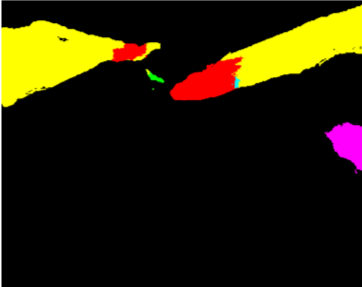

Our challenge was made up of 3 sub-problems. The first was binary instrument segmentation, where each frame was separated into da Vinci Xi instruments and a background class, which contained an ultrasound probe, surgical clips and porcine tissues. The second task was instrument part segmentation, where we scored the participants on whether they could correctly segment each articulating part of the instrument (see Fig. 3). Our final task was to segment and classify the instruments (see Fig. 4).

We provided the first 225 frames of 8 sequences as training data and kept the last 75 frames of those 8 sequences as test data. 2 of the full 300 frame sequences were kept as test sequences. Test labels were kept hidden from the participants. Our datasets contain 7 different robotic surgical instruments. The Large Needle Driver, Prograsp Forceps, Monopolar Curved Scissors, Cadiere Forceps, Bipolar Forceps, Vessel Sealer and additionally a drop-in ultrasound probe, which is typically held in the jaws of the Prograsp Forceps instrument. Samples from the training datasets are depicted in Fig. 2 and examples of the different instrument types are shown in Figure 3 and 4.

IV-C Parts Segmentation

Our second challenge was on instrument part segmentation where the participants were challenged to divide the binary instrument labels into a shaft, wrist and jaws. As in the binary segmentation challenge, the drop-in US probe and other man-made devices as well as all anatomical objects were to be labelled as background. We compute the mean IoU for each frame of each dataset and for frames where no instance of a class occurred, such as when the shaft is withdrawn completely from the field of view. Nine teams participated in this challenge, the only team abstaining was from IIT Delhi.

In Fig. 11 we show qualitative results from 6 datasets with randomly chosen method outputs for each frame. Again the vessel sealer instrument causes numerous problems with inconsistent labelling occurring all over the shaft.